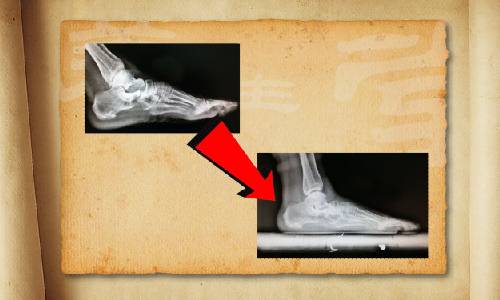

BTV養(yǎng)生堂人民醫(yī)院專家團選鞋選健康

【byb.cn 】(來源:BTV)2014年9月14日,BTV養(yǎng)生堂邀請北京大學人民醫(yī)院專家團的部分成員,就鞋與腳病之間的關系,糖尿病足,拇指外翻,腳墊等,共同制作了一期節(jié)目《選鞋選健康》,敬請收看~~!

很多足部的疾病,都是因為選鞋不當而導致的。有人做過統(tǒng)計:70%的人一生中有過腳病。比如腳部皮膚病變,真菌感染引起"腳氣";還可能受到各種損傷,引起骨折和肌腱的斷裂,或者出現(xiàn)后天性畸形;更為嚴重的是,腳部疾病還會導致腰、背等全身骨骼肌肉的問題。更多精彩內(nèi)容敬請收看北京衛(wèi)視《養(yǎng)生堂》—《選鞋選健康》。

很多老年人覺得穿布鞋是最舒服的,其實布鞋以及一些沒有足弓支撐的拖鞋、涼鞋,都會導致足部的內(nèi)側疼痛,進而造成足弓的損傷,最常見的是走路時間長了開始腳疼。如果您疼痛的部位,出現(xiàn)在腳掌中指下部、拇指跟部、小指跟部、中指關節(jié)處這些地方,您要千萬注意了。更多精彩內(nèi)容敬請收看本期節(jié)目。

我們都知道買鞋得看號碼,有經(jīng)驗的人買鞋會更有經(jīng)驗,比如皮鞋會買大一號,穿起來寬松;運動鞋呢就盡量合腳一些。但是大多數(shù)人不知道的是,買鞋不光要看鞋號,還要看鞋型。要依據(jù)自己的腳型來匹配買鞋。

沒有鞋帶的鞋,會存在踝關節(jié)損傷的隱患。老年人的腳踝是脆弱的,沒有鞋帶的保護,會發(fā)生很多意外的扭傷。更多精彩內(nèi)容敬請收看9月14日北京衛(wèi)視《養(yǎng)生堂》—《選鞋選健康》。